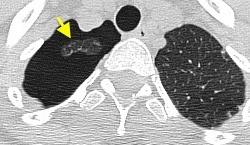

59. HEMATOCRITO EN ESPACIO PLEURAL, SIGNO DEL

En el hemotórax, los elementos formes de la sangre tienden a depositarse en la parte más declive